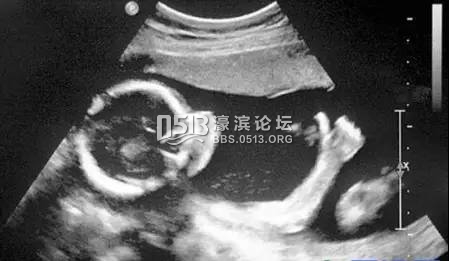

4、腹部盆腔——除肠道外,一般超声都能查

' o/ k3 B8 q. z1 z. C腹腔器官受呼吸影响较大,进而影响到CT、核磁成像,而超声不会因此受影响。同时,超声对肝脏、脾脏、胰腺、肾脏、盆腔脏器等诊断准确率较高。% [3 v0 o I; W c: e3 J8 b

但是超声受气体干扰很大,对于肠道等含气较多的器官,超声诊断准确率会降低。. b5 y" Q, d. f3 q